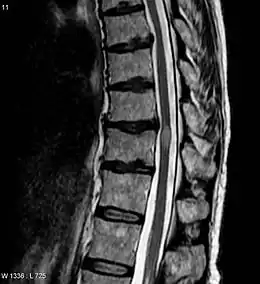

IRM de la moelle spinale montrant — la lésion est l'ovale grisé, au centre droit de l'image — une myélite transverse. Trois mois après cette image, le rétablissement était satisfaisant.